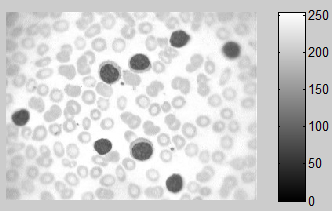

绿色频道,其实也显示了很大的对比(这让我很惊讶)

红色和蓝色通道很难真正区分细胞。

现在我们有两个候选人代表饱和或绿色通道,我们问谁更容易处理?由于任何HSV工作涉及到我们转换RGB图像,我们可以忽略它,所以明确的选择是简单地使用RGB图像的绿色通道进行分割。